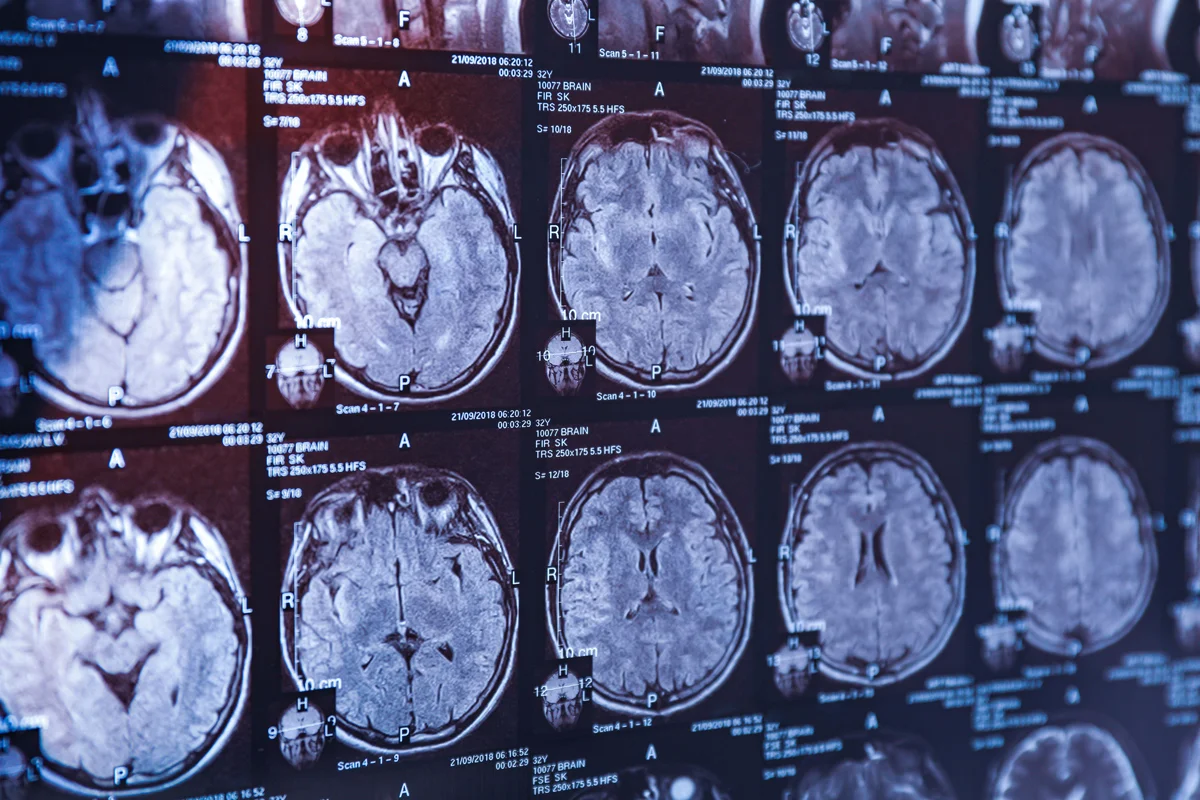

Фото: Warodom Changyencham / Alamy / Vida Press

Болезнь Паркинсона — это нейродегенеративное заболевание центральной нервной системы, которое проявляется в виде тремора (дрожания рук), скованности и замедленности движений. Симптомы напрямую связаны со скоплением альфа-синуклеина — белка, который регулирует работу нейронов и присутствует в мозге у всех людей, но в силу пока неясных причин может принимать патологическую, «слипающуюся» форму. Такие патологические белки начинают скапливаться в мозге и губительно воздействуют на нейроны. Это длительный процесс, но его проявления становятся видны лишь когда подавляющее большинство нейронов погибло.

Микро- и нанороботы могут решать массу задач в медицине — доставлять лекарства в самые труднодоступные органы и ткани или проводить хирургические операции там, где человек-хирург бессилен. Например, при кровоизлиянии в мозг — состоянии, которое требует немедленного реагирования, а в тяжелых случаях и вмешательства нейрохирурга. Наноробот с этой задачей может справиться лучше, поскольку для него не существует слепых зон и он может выполнять процедуры на клеточном уровне. Самый тонкий момент в этом — точная навигация: как заставить робота перемещаться по кровеносным сосудам в заданном направлении и без вреда для них. Ведь кровоток может вынести наноробота совсем не туда.

Эту задачу удалось решить исследователям из Университета Саскачевана под руководством профессора Криса Чжана. Ученые полностью пересмотрели принципы взаимодействия жидкости и твердого тела, доказав, что они оказывают влияние друг на друга в процессе движения. Далее на основе физико-математического анализа исследователи рассчитали оптимальные размеры и форму «виртуального хирурга». В результате был сконструирован наноробот спиралевидной формы, благодаря которой он может продвигаться в сосудах вращательными движениями, подобно штопору. Такая модель позволяет достигать самых мелких кровеносных сосудов в самых труднодоступных участках головного мозга и устранять нарушения.

В ближайшее время ученые планируют клинические испытания своей технологии. Если все пройдет успешно, медицина сможет справляться не только с последствиями геморрагического инсульта, но и с неоперабельными опухолями головного мозга, до которых хирургический скальпель не может добраться.